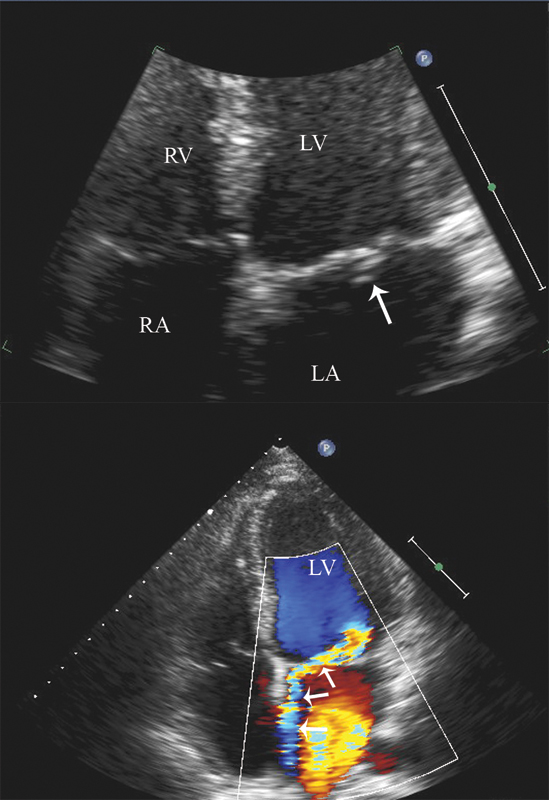

فحوصات تشخيصية لبعض امراض القلب والشرايين التاجية